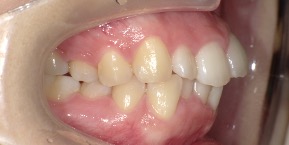

26歳女性のビフォーアフター

| 診断 | 空隙,叢生 |

| 治療方針 | 治療方針:前歯の咬合関係改善と空隙閉鎖を主な目的にて主にIPR(歯と歯の間をわずかに削合してスペースを獲得する方法)を組み込んだ動的矯正治療を行い、空隙、前歯咬合を改善後、保定を行う。臼歯部の咬合関係はプランの都合上維持することとした |

| 治療費 ※ | 69万8千円(診断、型取り、矯正中のメンテナンス、保定装置を含む料金) |

| 治療期間 | 1年8か月 |

| リスク | 1日20時間以上マウスピースを使用できない場合、歯が動かなかったり、想定しない誤差により不完全に終わる可能性がある。装着時や食事時に痛みを伴う。歯肉退縮や虫歯になるおそれがある。また、指導通りに装着できていない場合や適切なブラッシングが出来ていないとそのリスクが高くなる。歯根が短くなることがある。ごくまれに歯の神経が損傷してしまうことがある。過去にぶつけたり深い虫歯治療をしたことがあるとそのリスクはやや高くなる。矯正後には保定装置が必要。適切な使用ができない場合、後戻りの原因となる。将来的に歯並びが動いて再矯正が必要な場合がある。舌癖(舌で歯を押し出す癖)親知らずが正常に生えていない場合、その可能性がやや高くなる。 |